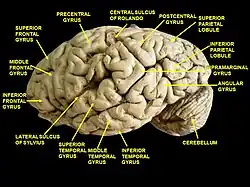

In neuroanatomy, the superior frontal gyrus (SFG, also marginal gyrus) is a gyrus – a ridge on the brain's cerebral cortex – which makes up about one third of the frontal lobe. It is bounded laterally by the superior frontal sulcus.[1]

The superior frontal gyrus is one of the frontal gyri.

Position of superior frontal gyrus (shown in red)

Position of superior frontal gyrus (shown in red) Left cerebral hemisphere seen from above

Left cerebral hemisphere seen from above Lateral surface of left cerebral hemisphere

Lateral surface of left cerebral hemisphere Medial surface of left cerebral hemisphere

Medial surface of left cerebral hemisphere Cerebrum. Lateral view. Deep dissection. Superior frontal gyrus labelled at top-left.

Cerebrum. Lateral view. Deep dissection. Superior frontal gyrus labelled at top-left. Medial surface of right cerebral hemisphere.